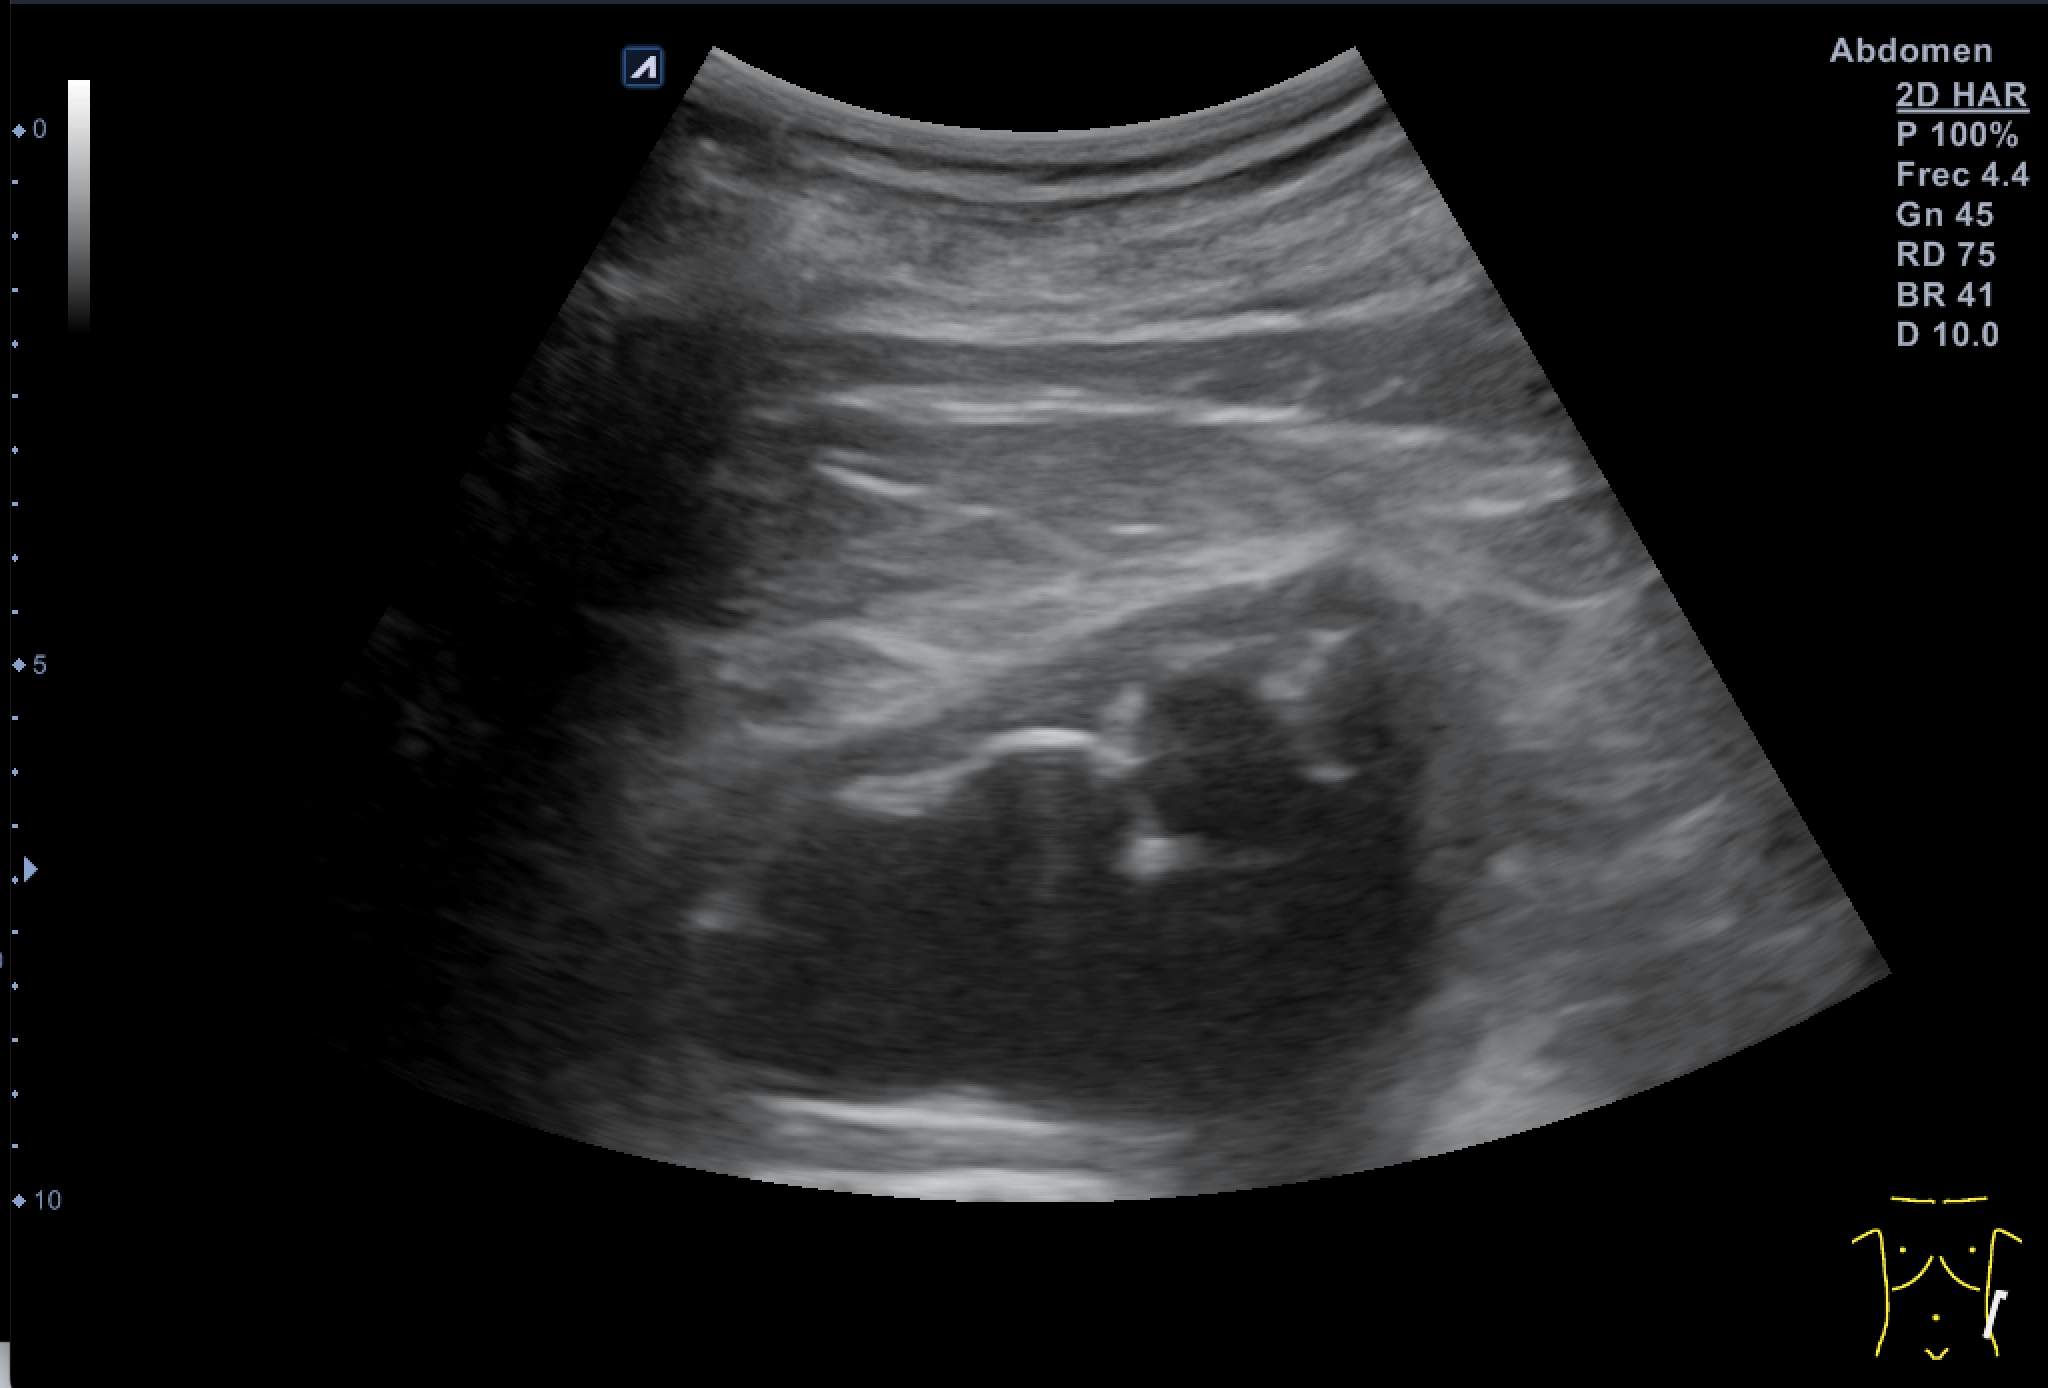

Tras valoración vesicoprostática con vejiga normal, jet vesicales visibles con próstata de 45 cc y residuo postmiccional mínimo. Riñón derecho como normal de tamaño y morfología sin dilataciones pielocaliciales (11 cm de tamaño). El Riñón Izquierdo (RI: 9 cm) presentaba una hidronefrosis grado IV y atrofia cortical con pelvis renal distendida, no consiguiendo detectar la causa obstructiva y considerando la posibilidad de una estenosis de la unión pieloureteral y como segunda opción una litiasis  ureteral pese a la normalidad de los jets vesicales.

En el estudio Uro-TC se aprecia según informe hospitalario (radiodiagnóstico), que la arteria renal izquierda tiene una división precoz de sus ramas, dando una rama para el polo inferior que impresiona de ser la causa de la compresión etrinseca en la unión pielocalicial.

Siendo la conclusión: hallazgos compatibles con estenosis de la unión pieloureteral izquierda, probablemente secundaria a una rama arterial para el polo inferior